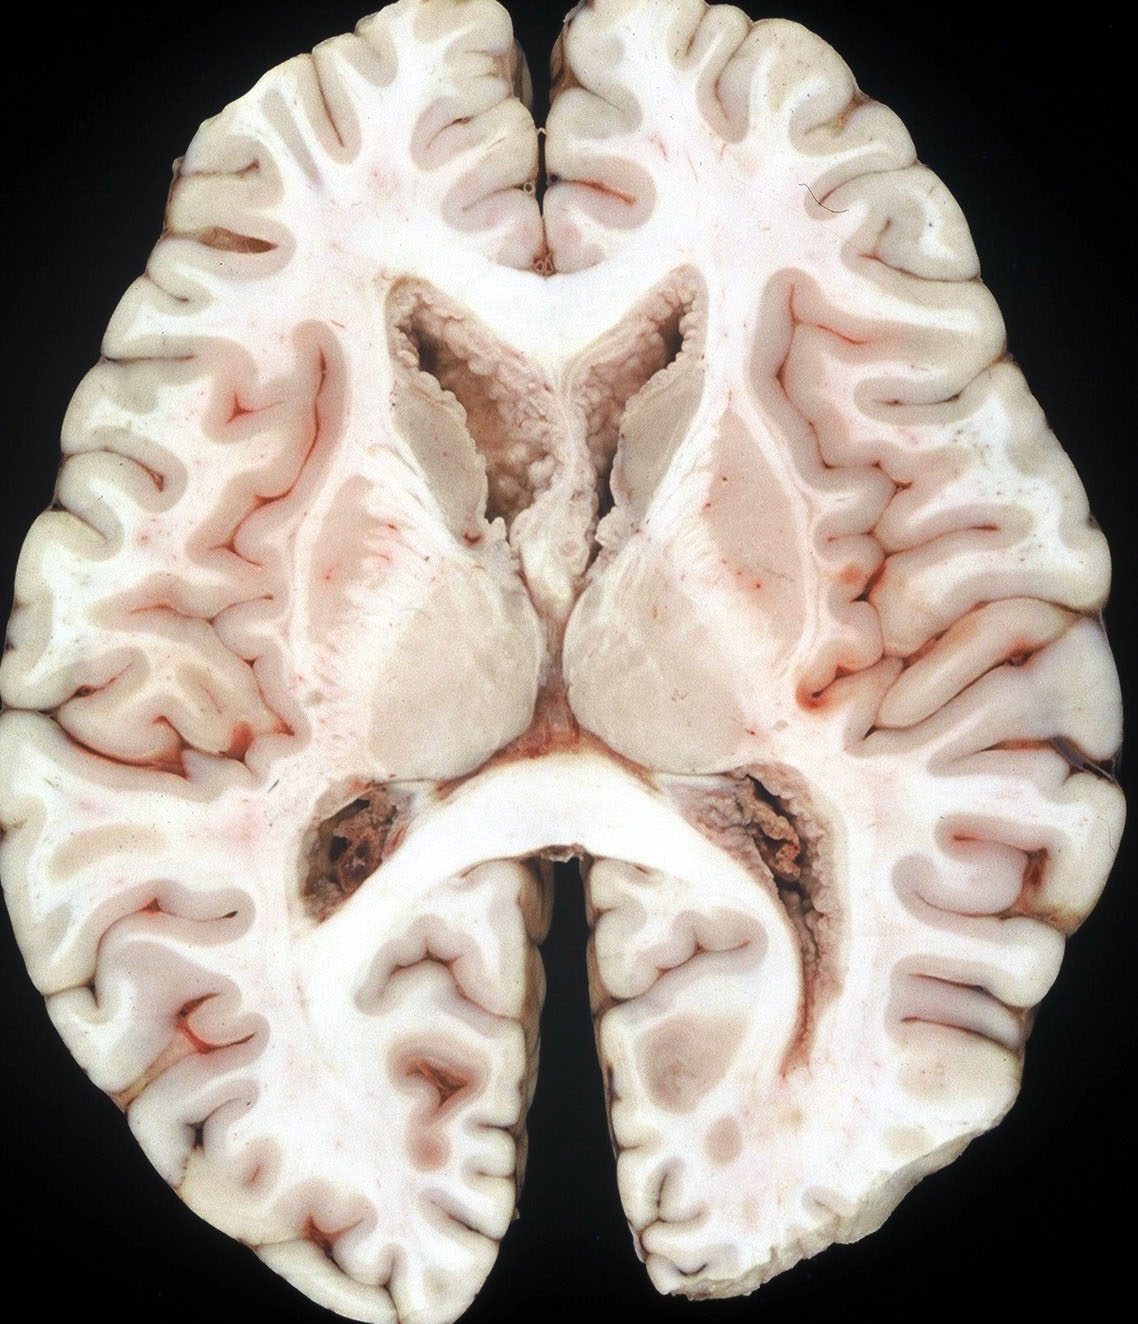

1992年の剖検所見

大脳表面,脳幹部,脊髄くも膜下腔には腫瘍が見当たりませんが,側脳室を充満するように腫瘍が増殖しています。

側脳室壁に結節状の腫瘍が無数に認められます。これは今日では,内視鏡による脳室内観察で見ることができるものです。

上方が側脳室側です。脳との境にある脳室上衣 ependyumの下に腫瘍細胞が這うように浸潤しています。そこから血管周囲 Virchow-Robin spaceを通って脳深部に浸潤しています。

大脳深部(左)と小脳深部(右)には髄質血管に沿って浸潤します。これは髄芽腫などと同様の脳浸潤所見です。